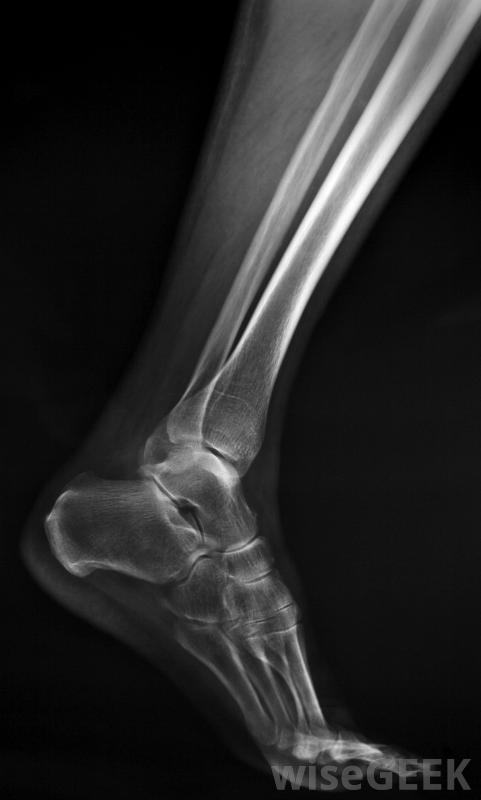

腓骨手術治療腓骨骨折或缺損,小腿骨,或獲取移植材料。手術的具體細節取決于患者為什么需要手術。可能由足踝專家、骨科醫生進行,或者是神經外科醫生。康復時間從幾個小時到幾周或幾個月不等,通過物理療法來重建患肢的力量。如果患者想了解更多關于治療方案和醫生建議的信息,他們可以在手術前向其他外科醫生尋求第二意見腓骨是小腿中較薄的長骨,需要進行腓骨手術的一個常見原因是修復骨折沿著小腿外側延伸至腳踝,通常在踝關節附近骨折。有些骨折可以通過石膏固定修復,但其他骨折可能需要手術治療。這包括在骨骼編織時用釘住骨頭使其穩定,以及檢查韌帶、肌腱的損傷,這種損傷可以在腓骨手術中得到糾正。腓骨手術后,腿通常被固定在石膏中另一個可能出現在腓骨周圍的問題是神經卡壓,這可能導致刺痛感、疼痛或無法控制腳神經外科醫生可能會建議腓骨手術來釋放被困的神經并重新定位,這樣患者就不太可能再次出現這種問題。其他的手術可以解決諸如:受傷后腓骨周圍韌帶撕裂;骨骼形狀異常;或關節炎和感染引起的損傷修復骨折是進行腓骨手術的最常見原因腓骨植入身體其他部位。在骨移植手術中,病人被麻醉,同時采集材料樣本并植入新的位置,如頜骨。這可以在嚴重損傷后重建骨骼,或者作為矯正手術的一部分來解決先天性畸形。在這種情況下,手術團隊可能會包括重建外科醫生來創造一個平滑而均勻的外觀。手術所需的麻醉水平可能會有所不同。對一些人來說,只有清醒鎮靜和局部麻醉劑是必需的。其他人需要全身麻醉以確保病人的安全,這通常會導致較長時間的恢復。患者應在腓骨手術后盡快進行活動,以降低血栓的風險,并開始重建腿部的力量。建議他們考慮將物理治療作為恢復的一部分腓骨手術對于修復腓骨(小腿的一塊骨頭)的骨折或缺損是必要的。